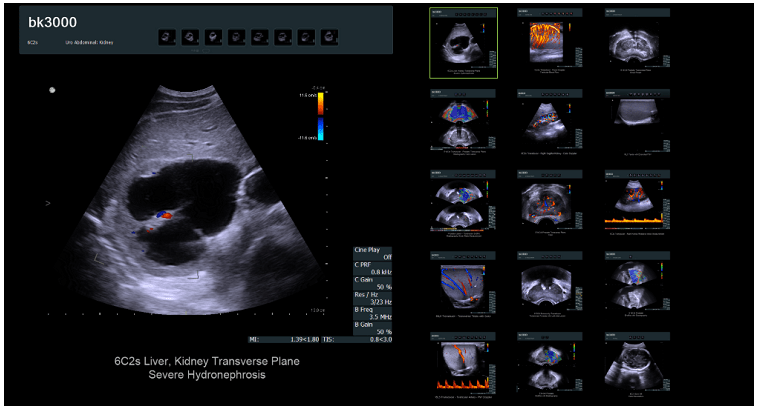

该在线商店出售现代且昂贵的设备(超声波机器)。目标受众不需要号召性用语,不需要标准的潜在客户生成按钮或评论形式的信任块。产品的详细和专业描述在这里起着关键作用,它将表明其功能,功能和优势。

同意,此产品卡与我们以前所见的产品根本不同。但同时,它完全可以满足目标受众的需求。用于联系卖家的潜在客户生成按钮促成销售,并允许您增加网站的转化率。